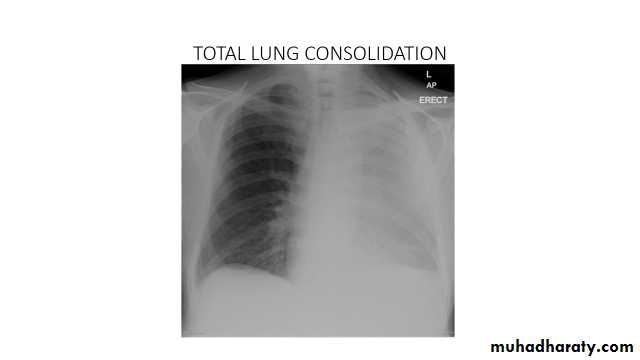

Total lung collapse